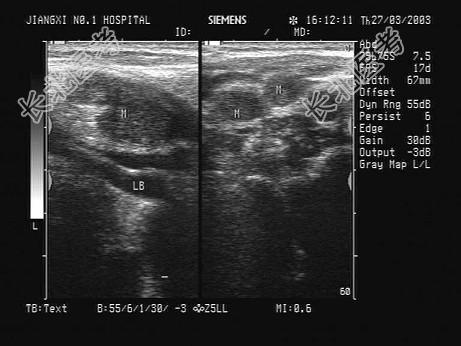

- 单项选择题患者发现颈部肿块两年余,没有明显不适。甲状腺超声显示甲状腺及血管旁异常光团, 如图。最可能的诊断为 ( )